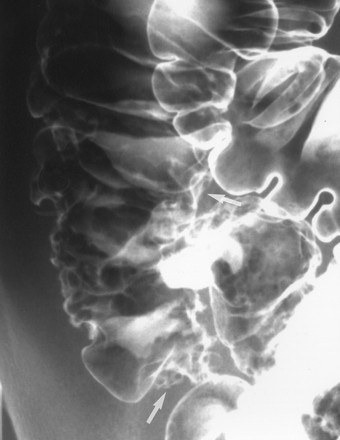

Viêm đại tràng do lao có hình ảnh giống bệnh Crohn, bệnh hiếm ở người da trắng nhưng hay gặp ở người châu Á và bệnh nhân AIDS. Mặc dù phần lớn là thứ phát sau lao phổi, nhưng đa số bệnh nhân không có bằng chứng lao phổi trước đó hoặc lao phổi hoạt động. Với bệnh nhân châu Á, phần lớn bệnh nhân lao ống tiêu hóa là do nuốt trực khuẩn lao bò. Chẩn đoán trực khuẩn kháng axit hoặc u hạt hoại tử bã đậu có độ nhạy thấp (khoảng 32% và 50%, tương ứng) [9]. Với sự hiểu biết tốt hơn về các đặc điểm của viêm lao đại tràng, chẩn đoán sớm bằng chụp cản quang kép là có thể [10]. Các đặc điểm sớm của lao đại tràng là co thắt, tăng tiết, tăng nhu động, tăng sản lympho, các nếp dầy, và các vết loét nông (Hình 18). Các dấu hiệu của viêm lao đại tràng tiến triển khi chụp cản quang kép bao gồm các vết loét ngang (Hình 19), các nốt, các nếp dầy, polyp viêm hoặc sau viêm, hẹp và biến dạng vùng hồi-manh tràng (Hình 20).

Hình 18. Bệnh nhân nữ 16 tuổi bị lao đại tràng giai đoạn sớm. Phim cản quang kép đại tràng ngang chụp gần bộc lộ các vết loét không đều có bờ nhô cao.

Hình 19. Bệnh nhân nữ 22 tuổi bị lao đại tràng giai đoạn tiến triển. Chụp cản quang kép bộc lộ các vết loét ngang và vết loét theo chu vi (mũi tên) ở vùng hồi-manh tràng và đại tràng lên.